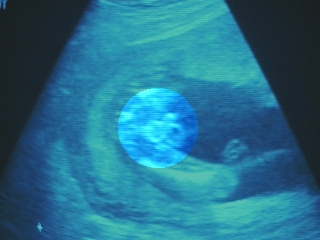

Week 9: Here's a Sonogram of "Pinto" at 9 weeks. We call it "pinto" because it is the size of a pinto bean! ;-)

S/He (it!) is the blob in the middle of the boomarang shaped image at the bottom. One can't really make out much on the sonogram ... but when you see it in real-time, you actually see the heart beat ... and every once in a while, it wiggles like a worm.

This may not look like much to you ... but rest assured that to the mother and father, it is *QUITE* cool!